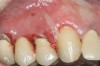

Oral manifestations feature formation of vesiculobullous lesions, a positive Nikolsky’s sign, and DG (Figure 6). Near­ly all individuals who develop MMP will have DG, and the gingiva may be the only site of involvement in more than 50% of cases38 (Figure 7).

Figure 7  MMP of the gingiva.

Figure 7